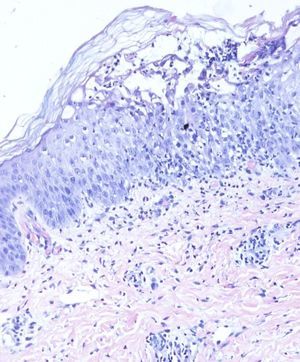

We report the case of a full-term baby girl with Down syndrome and a vesiculopustular rash located predominantly on the face, with lesions distributed unevenly on the face, scalp, and torso (Fig. 1). No prenatal tests were performed until the second half of the pregnancy, when ultrasound revealed mild heart abnormalities. Down syndrome was confirmed by karyotype in the first week of life. Tests carried out in the first week of life showed the following results: hemoglobin, 22.7g/dL; platelets, 46 000/μL; and leukocytes, 49 000/μL, with 28% blasts in blood. Cultures for bacteria, fungi, and viruses were negative. A smear of one of the pustules showed intermediate mature granulocytic elements and some blasts. The bone marrow showed no signs of leukemia. A skin biopsy revealed a subcorneal vesicular pustule filled with polymorphonuclear leukocytes and epidermal exocytosis (Fig. 2). Both the blood and skin abnormalities resolved spontaneously in the first weeks of life.